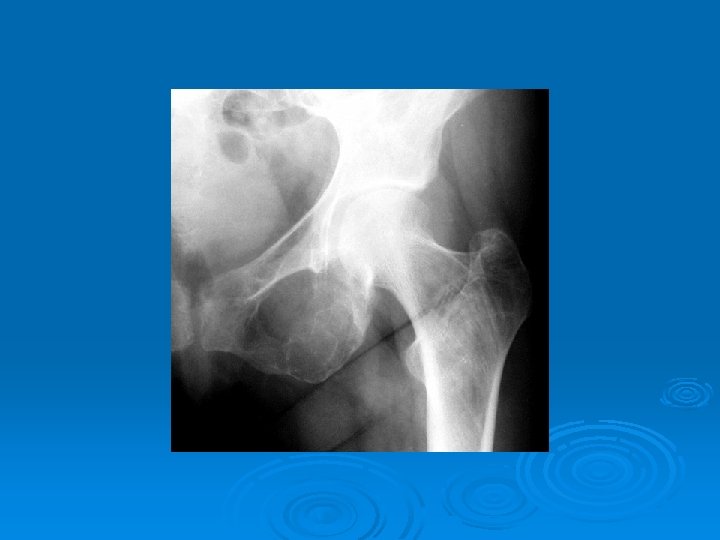

Imaging Studies Ø Ultrasonography and 99 m. Tc sestamibi scanning have the advantages of being widely available and relatively inexpensive compared but is operator-dependent. Ø Radiology ---- subperiosteal resorption at the radial sides of the phalanges, distal phalangeal tufts, and distal clavicles. Ø Skull Xray ---- pepar salt apperance . Ø (DXA) at the hip and spine ---- ostoprosis.